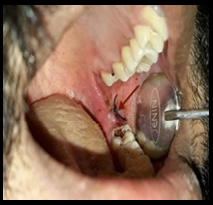

17)

Hemisection of Mandibular Molar: Hopeless to Hoping

Mridusmita Mukherjee, Mohamed Riyas AB

[Abstract] | [PDF Full Text]